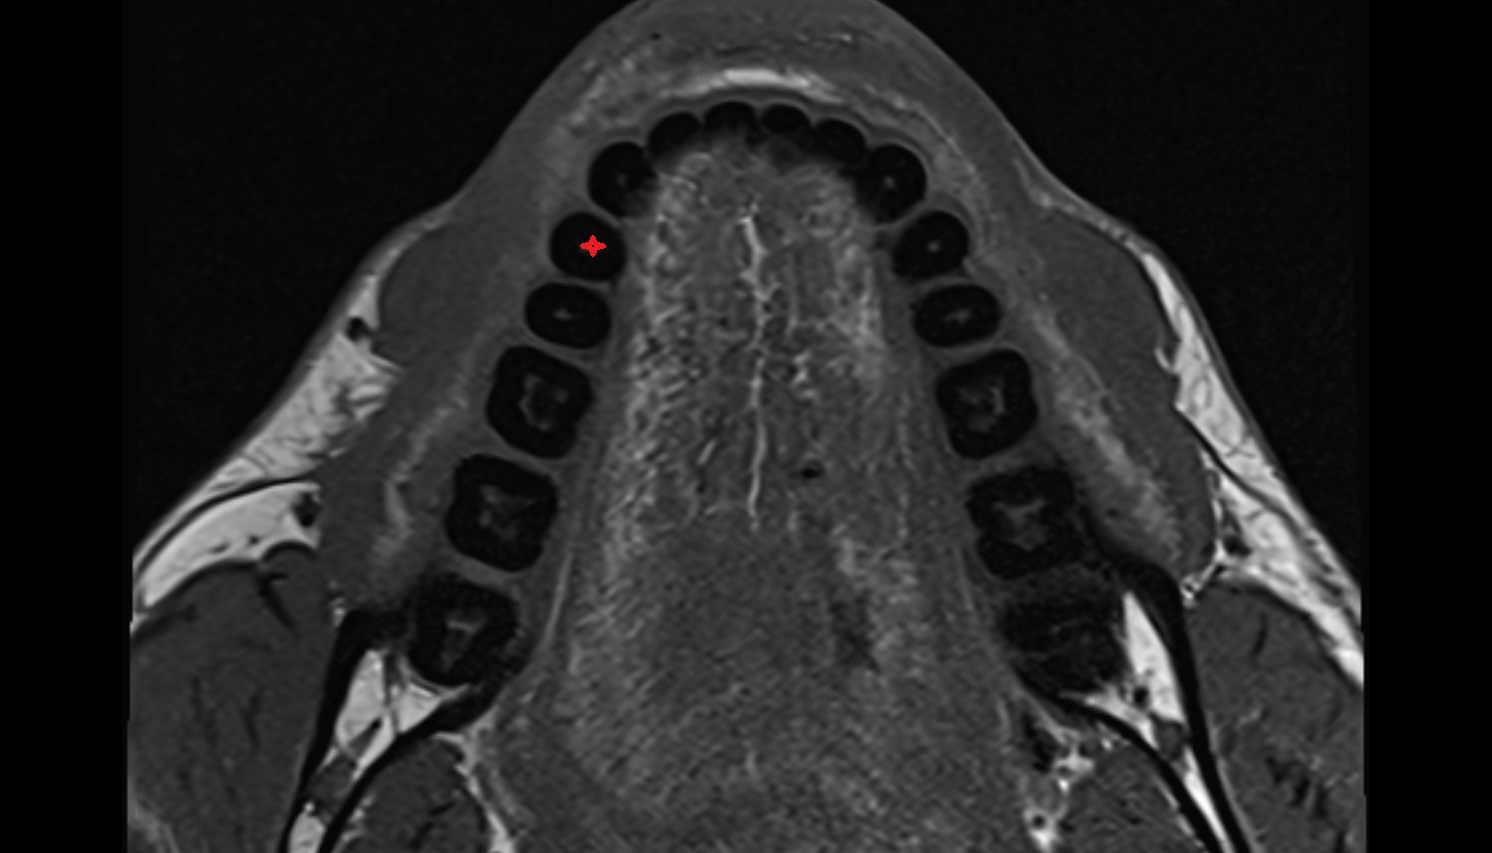

- Central inferior incisor tooth

- Central superior incisor tooth

- Inferior canine tooth

- Lateral inferior incisor tooth

- Lateral superior incisor tooth

- superior canine tooth

- Superior first molar tooth

- Superior first premolar tooth

- Superior second molar tooth

- Superior second premolar tooth

- Superior third molar tooth

- Root of lower molar tooth

- Root of upper molar tooth

- Root canal of upper molar tooth

- Dental pulp of upper molar tooth

- Dental pulp of upper premolar tooth

- Root canal of upper premolar tooth

- Root canal of upper canines tooth

- Enamel of upper molar tooth

- Enamel of upper incisor tooth

- Alveolar ridge

- Alveolar process of maxilla

- Superior dental plexus